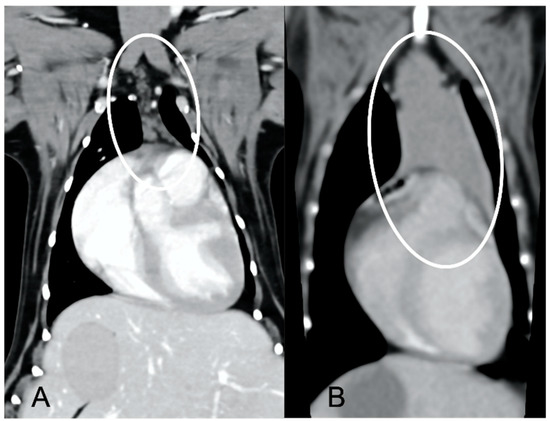

The overall appearance was lobulated in all of the adult dogs and homogeneous in all of the juvenile dogs (Figure 1 and Figure 3). The thymus was left-sided in all of the adult dogs, while it was located in the midline in a few juvenile dogs; one presented a thymus on the right side due to situs inversus (Figure 4). The maximum dimension of the thymus in the adult dogs group was always the length, while in some juvenile dogs, the maximum diameter was the width (Figure 2). The dimensions of the thymus were variable between different patients, with several breeds included and large differences in body weight between the dogs. For this reason, a ratio between the maximum diameter of the thymus (measured in cm) and the body weight (measured in kg) was calculated for each dog. The median ratio in the adult dogs group was 0.2 (minimum: 0.06; maximum: 0.4), while in juvenile dogs, it was 0.4 (minimum: 0.1; maximum: 1.4). The dogs with the higher ratio (>1) were in the juvenile group and they presented with spinal a cyst and enteritis and were 6 and 7 months old, respectively. The dogs with the lower ratio (<0.1) were in the adult group and they presented with muscular hemangiosarcoma (one dog) and synovial cell sarcoma (two dogs) and were 2, 6, and 8 years old, respectively.

The thymus was less attenuating in adult dogs compared to young dogs, with a median of the mean pre- and post-contrast attenuation values lower in adult dogs compared to juvenile dogs (Table 1). In 5/11 (45%) adult dogs, the minimum pre-contrast attenuation values were negative values (from −22 to −2 HU), due to the presence of multiple, hypoattenuating, thick septi within the thymic parenchyma (Figure 5).

Several CT features of thymic neoplasia have been described in dogs. Thymomas have been described as large, space-occupying masses arising from the cranial mediastinum, frequently heterogeneous or with a cystic appearance, mainly left-sided but being more centrally located with increasing size [6]. Vascular invasions have been reported, especially in larger masses [6]. Cranial mediastinal lymphomas have been described as more homogeneous masses compared to thymic epithelial neoplasms, more likely to envelop the cranial vena cava [7]. The CT characteristics of thymic neoplasia reported in these previous studies, such as large masses, heterogeneous, enveloping or invading the adjacent vasculature [6,7], were significantly different from the findings of the current study, in which the thymus was in fact considered non-neoplastic. The CT appearance of thymic hyperplasia in humans can be variable, but some features, such as bipyramidal morphology and the presence of gross intercalated fat (also described as ‘marbling’), are considered pathognomonic [20]. This appearance of ‘marbling’, with the presence of several hypoattenuating septations throughout the thymic parenchyma, was present in all of the adult dogs included in the current study, suggesting that these dogs may have presented with thymic hyperplasia at the time of CT examination.

Figure 4. Lateralization of the thymus (circled) in two dogs. Post-contrast dorsal CT reconstructions. A mainly left-sided thymus in an adult dog (A) compared to a mainly right-sided thymus in a young dog (B) with situs inversus.

Figure 5. Appearance of the thymus (circled) in an adult dog. Post-contrast transverse CT image (A) and dorsal reconstruction (B). Note the presence of multiple hypoattenuating septi within the parenchyma, giving the thymus a lobulated appearance and overall low attenuation.